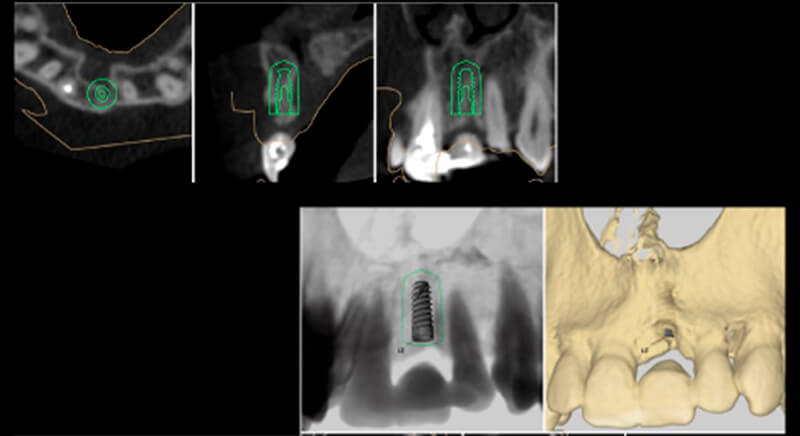

During the digital planning for the implant, with Implant Studio (3Shape) guided surgery software, significant bone defects due to the patient's anatomy were discovered. Placing the implant in the correct position for the prosthesis presented bone dehiscence in the vestibular area, and another bone defect in the palatine area due to the patient's large nasopalatine canal.

This information enabled us to rule out the option of surgery without a flap, as regeneration simultaneous to surgery would be needed, so the idea of using guided surgery was maintained.

The guided surgery was performed by lifting a full thickness mucoperiosteal flap. A Biomimetic Ocean CC implant, diameter 3.5mm and length 10mm, was inserted using the surgical guide in the ideal three-dimensional position and the defects were regenerated with xenograft and reabsorbable membrane, the nasopalatine duct on the palatine side and the area of dehiscence on the vestibular.